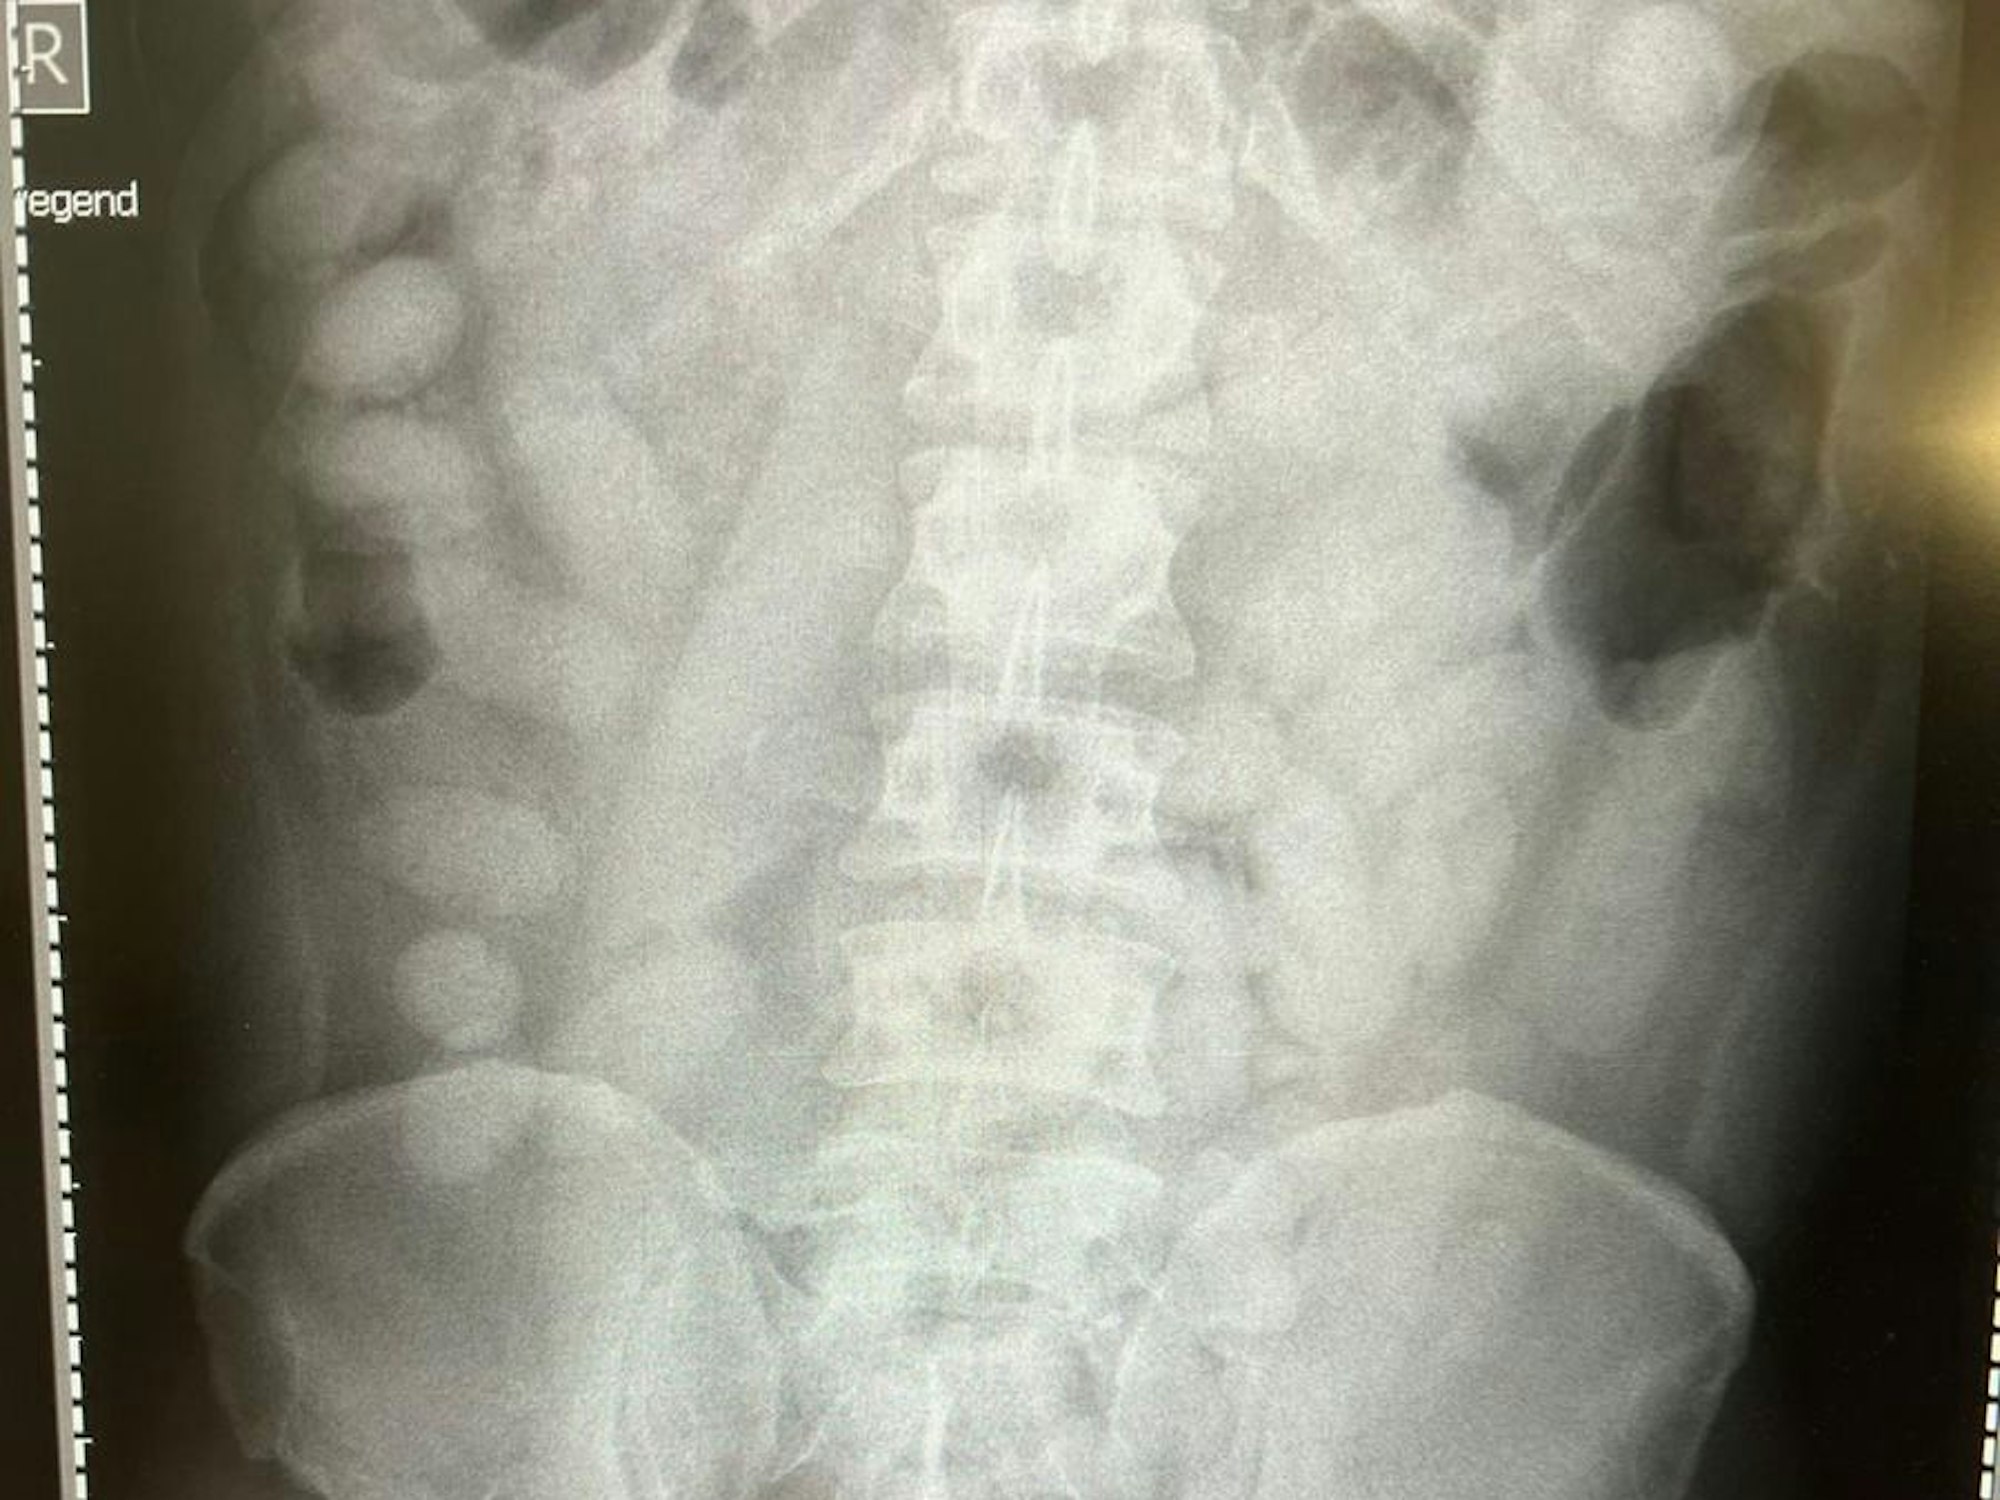

Auf dem Röntgenbild sind die Drogenpäckchen gut zu sehen. Der Mann (39) war am 26. November 2021 Kölner Zöllner aufgefallen, als sie einen Reisebus auf einem Rastplatz bei Bad Honnef kontrollierten.

„Die Röntgenaufnahme in einem nahegelegenen Krankenhaus bestätigte letztendlich den Verdacht. Der komplette Magen-Darm-Trakt des Mannes war voll mit Drogenpäckchen, sogenannten Bodypacks“, so Jens Ahland, Sprecher des Hauptzollamtes Köln.

Nach dem Ausscheiden der Drogen war klar: Der Mann hatte insgesamt 72 Bodypacks, gefüllt mit jeweils knapp 14 Gramm Kokain, geschluckt. Jens Ahland: „Mehr als ein Kilogramm Kokain versteckt im Körper, ist für uns ein neuer trauriger Rekord.“